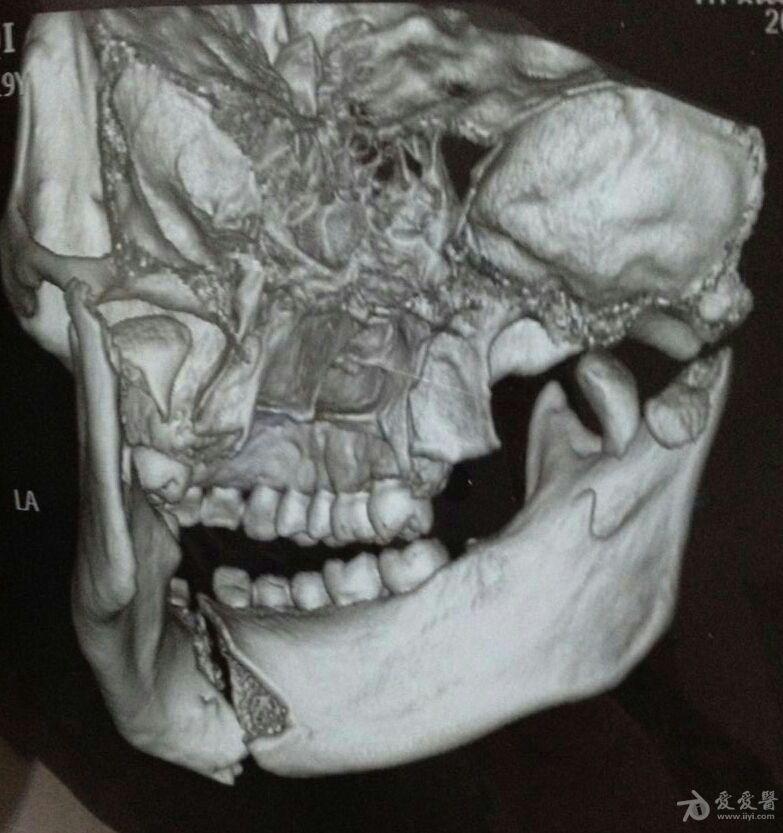

病例13:上颌关节骨折,颧骨骨折,乳突骨折以及颅底骨骨折诊断的诊断

面颅骨复杂性骨折求意见